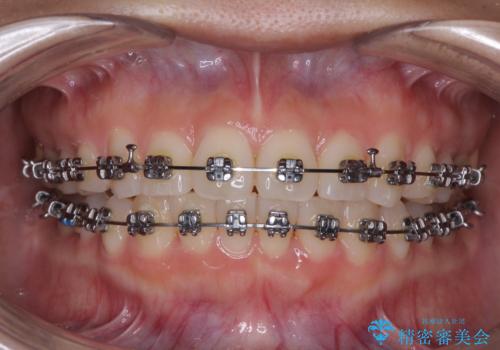

- 矯正装置

- メタルブラケット

治療中は大きなトラブルもなく、予定の1年半でスムーズに治療を終えることができました。